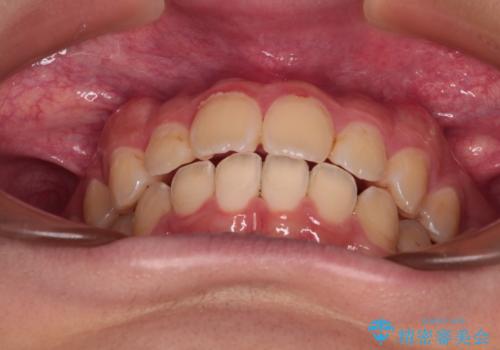

- 深く咬みこんだ前歯と、それに伴い前方に突出した上顎前歯を気にして来院された患者様です。

下顎の歯列は、奥歯が前方に傾斜し、前歯が上顎の歯の付け根に食い込むように内側に傾斜していました。

また、左右の犬歯の位置関係は上顎歯列が前方に位置する咬み合わせとなっており、インビザライン単体で治療するよりは、ワイヤー装置や補助装置を併用した方がより良い仕上がりになることが期待されました。